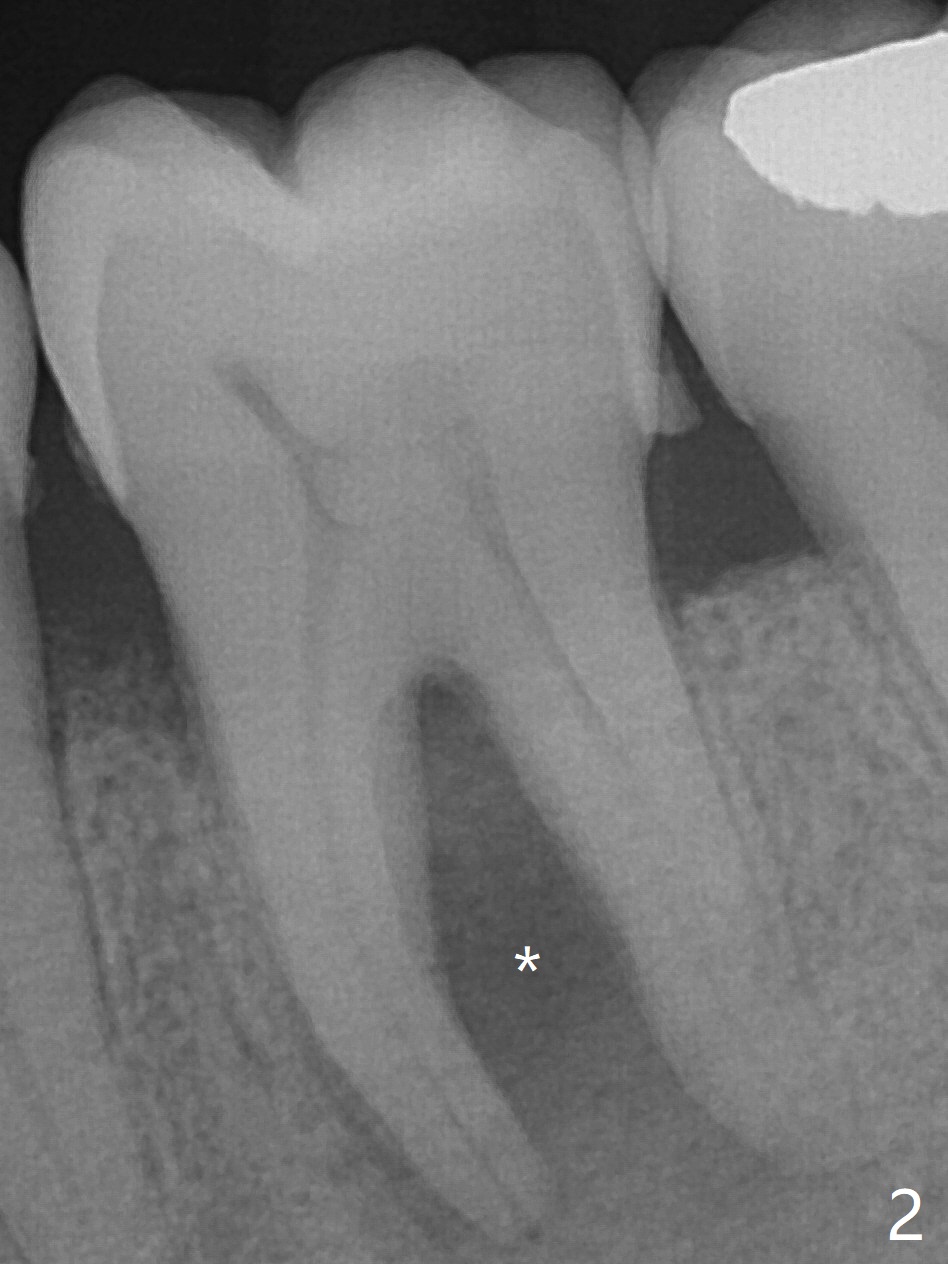

A 62-year-old man (smoker, 1.5 packs a day) has had no dental visit for 12.5 years (Fig.1). His chief complaint is pain at #19 after eating popcorn. The septal bone resorbes (Fig.2,3 *) with granulation tissue between the mesial and distal roots (Fig.4,5 *). Although there is no bony wall defect, the socket is single and large (9x9 mm, Fig.7). The largest (8 mm) cylindrical implant should not be able to obtain primary stability. The biggest challenge for immediate implant is ambiguous the Inferior Alveolar Canal (Fig.1,3 red dashed line). If there were no financial or time issue for immediate implant, CBCT should have been taken. Socket preservation is done instead with Vanilla graft, Human Amniotic Chorion Allograft (membrane) and Osteogen Plug (Fig.6). If he returns for SRP and implant, perform flapless bone expansion for osteotomy. When the patient returns 14 d postop, #19 socket is healing and filled with bone graft (Fig.8 (panoramic X-ray)). When he returns 14 months postop, the socket heals (Fig.9, as compared to Fig.6).